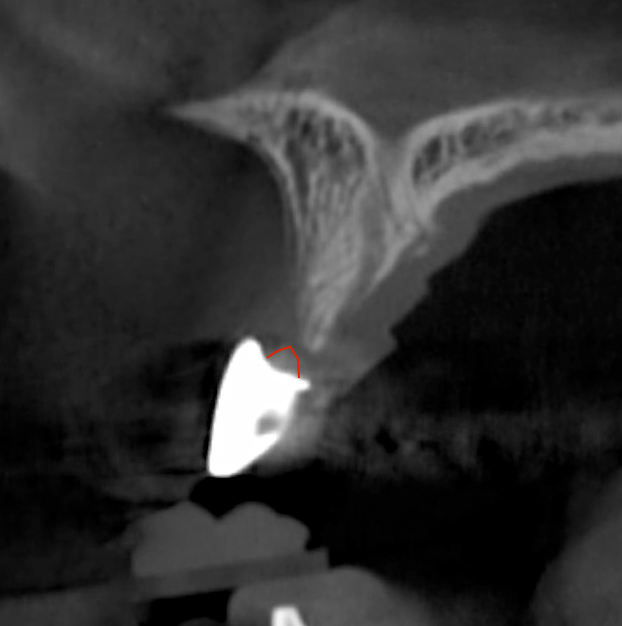

Tomographic images revealed a large tridimensional defect, with vertical and horizontal loss of bone extending to the apical third of teeth Nos. 6 and 8. Additionally, a buccal bone dehiscence was evident on tooth No. 5, and thin labial plates secondary to the orthodontic movement were present in several areas (Figure 3 and Figure 4).

Fig 3. Tomographic images revealed a tridimensional defect extending to the apical third of teeth Nos. 6 and 8, a buccal bone dehiscence on tooth No. 5, and associated thin labial plates.

Figure 3

Fig 4. Tomographic images revealed a tridimensional defect extending to the apical third of teeth Nos. 6 and 8, a buccal bone dehiscence on tooth No. 5, and associated thin labial plates.

Figure 4